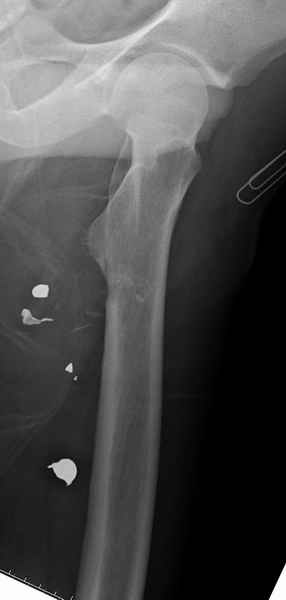

Больной с огнестрельным переломом бедра с вовлечением около 15% медиального кортекса, входное отверстие около 1 см в диаметре; стабильный, без сосудистых и неврологических признаков.

Учитывая, что больной получил травму не во время визита в церковь, и он является одним из представителем 40 миллионного “outstanding itizen”, без медицинской страховки, без работы в свои 39 лет, и без надлежающей ортопедической дисциплины у которого отсутсвует страх стрессового перелома, было рекомендовано оперативное лечение: профилактическое антеградное интрамедуллярное штифтование.

Методика штифтования при отсутствии большой зоны перелома как при онкологических профилактических штифтованиях, расверливание интрамедуллярного канала проводим с предварительным наложением дополнительного дренажного отверстия в дистальном отделе бедра (в данном случаи в канале оставили 6.5 мм канюлированный шуруп), иначе при создании давления в канале во время сверления имеется опасность эмболизации легочной артерии тромбом.